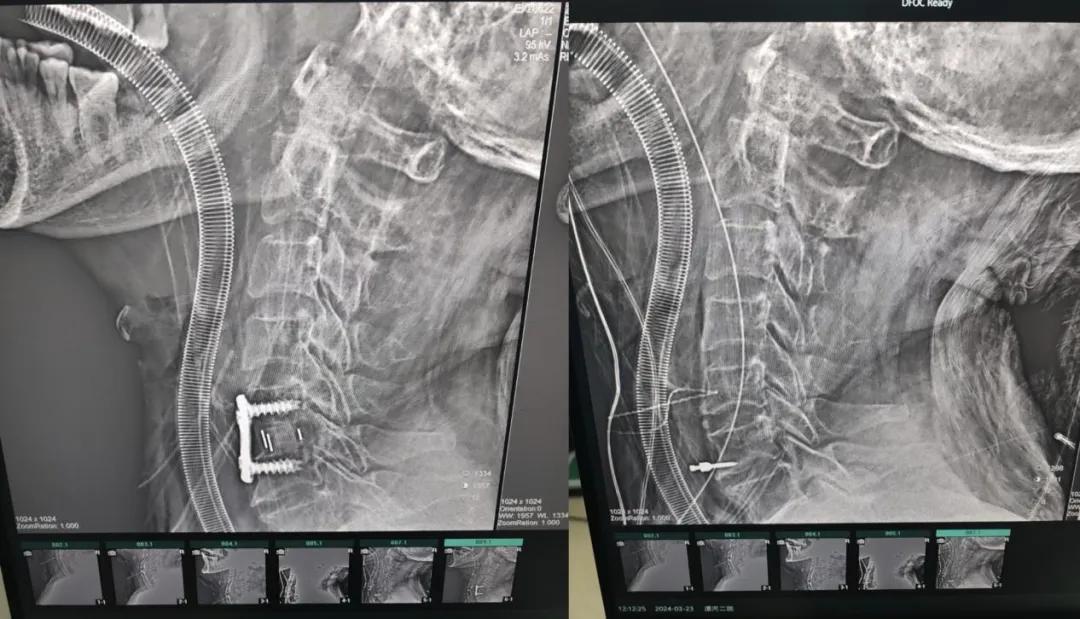

經過縝密的術前準備和手術計劃,在鄭大一附院神經外科張風江教授的指導下,神經外科團隊順利為患者實施“顯微鏡下頸椎前路C5/C6椎間盤切除椎間融合+內固定術”,手術時間不到1小時。術后患者恢復情況良好。